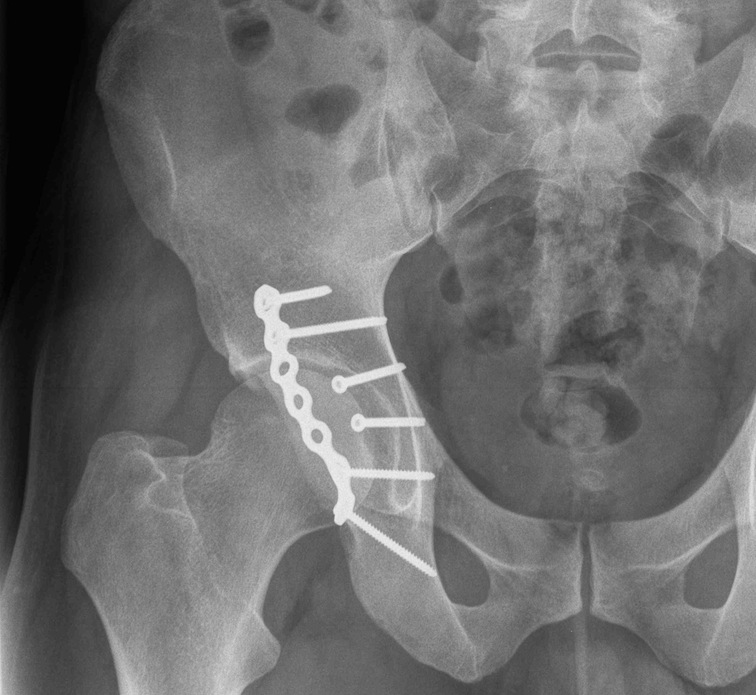

Anterior Column & Wall Fracture

ORIF

1. Reduce quadrilateral plate

- small T plate / will sit under pelvic reconstruction plate

- separate recon plate

2. Plate iliac crest fracture

- long 13 hole plate from pubis

- along superior pubic ramus up onto inner table of ilium

- indirect acetabular reduction